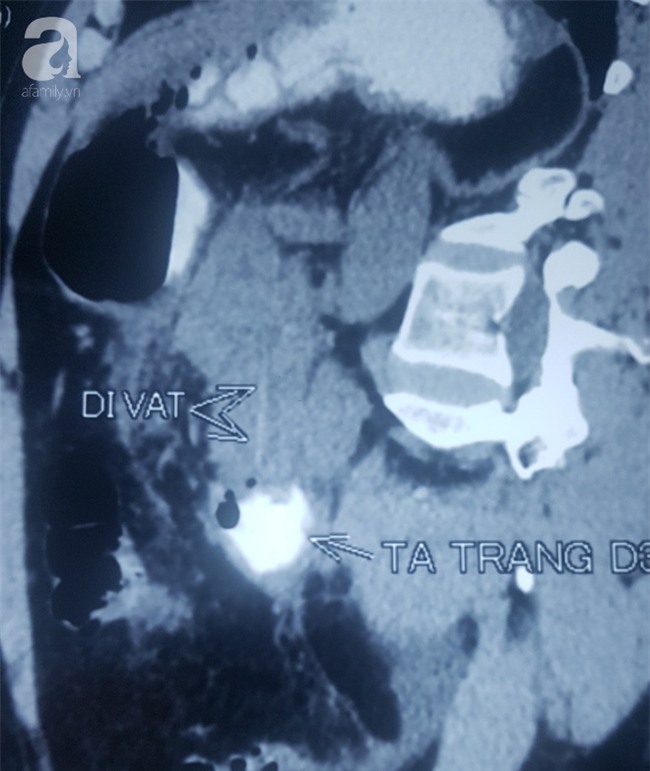

Đến khi đau bụng dữ dội, sốt nhiễm trùng nặng và uống thuốc nhưng không giảm, ông H.Q (51 tuổi, Q.Gò Vấp) mới đến Bệnh viện Hoàn Mỹ Sài Gòn cầu cứu. Sau khi khám, thử máu và chụp CT, các bác sĩ phát hiện dị vật dạng cây tăm đã đâm thủng tá tràng (ruột non) và đầu tụy của nạn nhân, gây nhiễm trùng nặng.

Các bác sĩ đã thực hiện nội soi cấp cứu nhưng chỉ lấy được phần dị vật đâm thủng lòng ruột non dài khoảng 3cm. Phần còn lại của cây tăm đâm vào đầu tụy đã bị nhũn ra không thể gắp được.